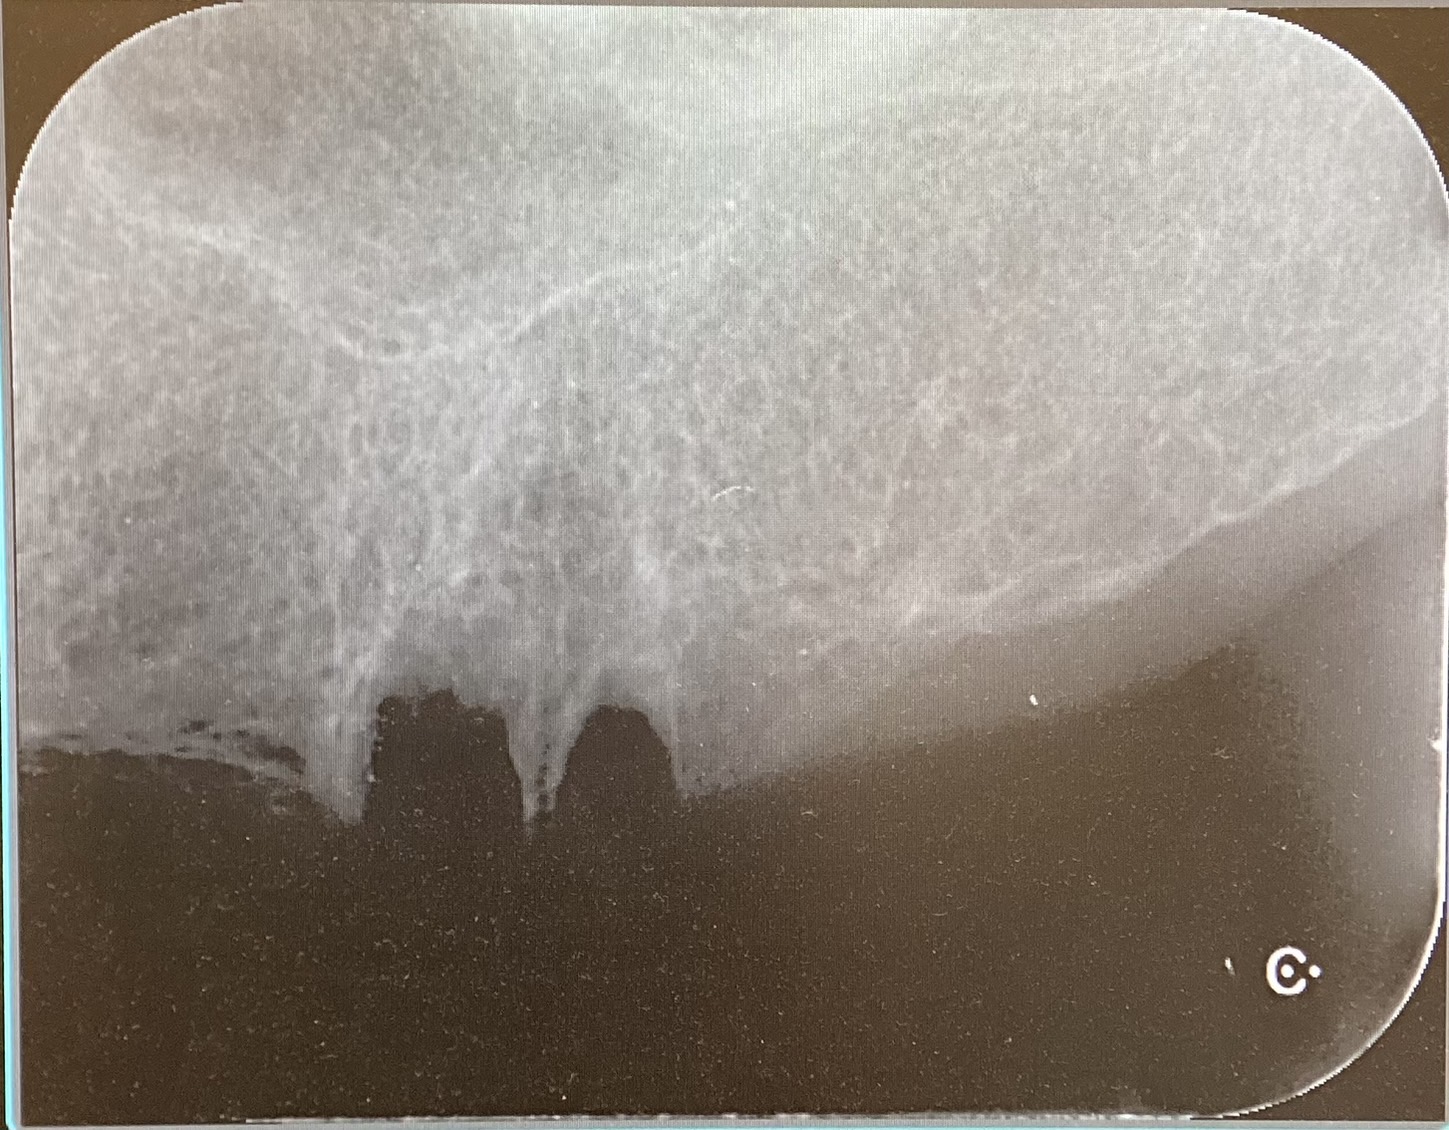

Before

抜歯当日にインプラントを埋入する治療です。

通常のインプラント治療は抜歯後3ヶ月程度、骨の治癒を待ってからインプラントを埋入します。

抜歯即時埋入は、抜歯当日にインプラントを埋入するため、治療期間を3ヶ月程度短縮することが出来ます。